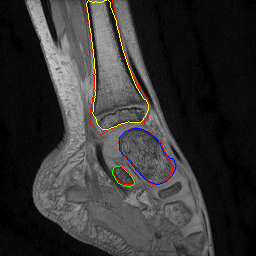

Fig. 2: Visual comparison of UNet regularization methods: baseline UNet [2], adversarial regularization [6], shape priors based regularization [7] and the proposed shape priors based adversarial regularization on ankle dataset. Ground truth delineations are in red (). Predicted bones, calcaneus, talus and tibia respectively appear in green (), blue () and yellow ().

Experiments were conducted on two pediatric datasets previously acquired using a 3T Philips scanner [4]. The two MR images datasets were independently acquired on two musculoskeletal joints (ankle, shoulder) from a cohort of 17 and 15 pediatric patients. An expert (12 years of experience) annotated images to get ground truth contours of calcaneus, talus and tibia for ankle, as well as scapula and humerus for shoulder. All axial slices were downsampled to 256×\times256 pixels.

We compared the proposed shape priors based adversarial regularization method (SPAR in Fig.1) with baseline UNet (Base. UNet) [2], adversarial regularization (Adv. Reg.) [6] and shape priors based regularization (Sh. Reg.) [7]. For all methods, the backbone UNet architecture and all training hyper-parameters remained the same. All networks were trained from scratch with randomly initialized weights.

From the quantitative results (Tab.1), our method achieved competitive results compared to state-of-the-art on both datasets. On ankle dataset, our approach ranked best in Dice (92.7%percent\%), RAVD (8.0%percent\%), ASSD (0.8mm) and MSSD (8.1mm) metrics. For shoulder dataset, our method outperformed other approaches in RAVD (13.6%percent\%) while remaining second best in Dice (0.3%percent\% lower than the best) and ASSD (0.3mm higher than the best). We suspected that the high variability observed in shoulder results was due to the poor quality of two outlier examinations. The visual comparisons (Fig.2) provided the evidence of gradual improvements in segmentation quality of the regularized methods over baseline UNet. We wanted to report statistical significance tests to compare the performance of the employed methods but the required sample size determined using a power analysis (with typical statistical power β=0.8𝛽0.8\beta=0.8) was larger than our available datasets.